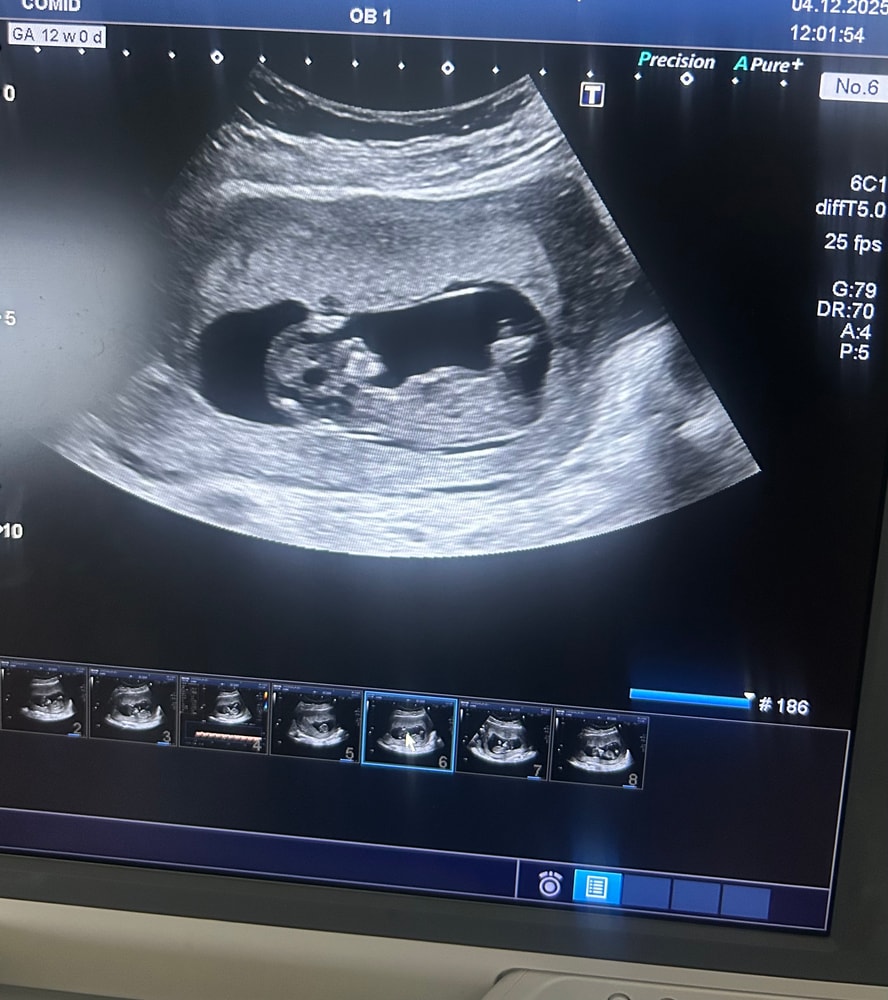

Пройдено узи, сдана кровь.

со слезами на глазах выходила с кабинета, слезы счастья.

мой малыш ❤️

по узи все хорошо 🙏🏼 Слава Богу

теперь осталось дождаться крови 🫣